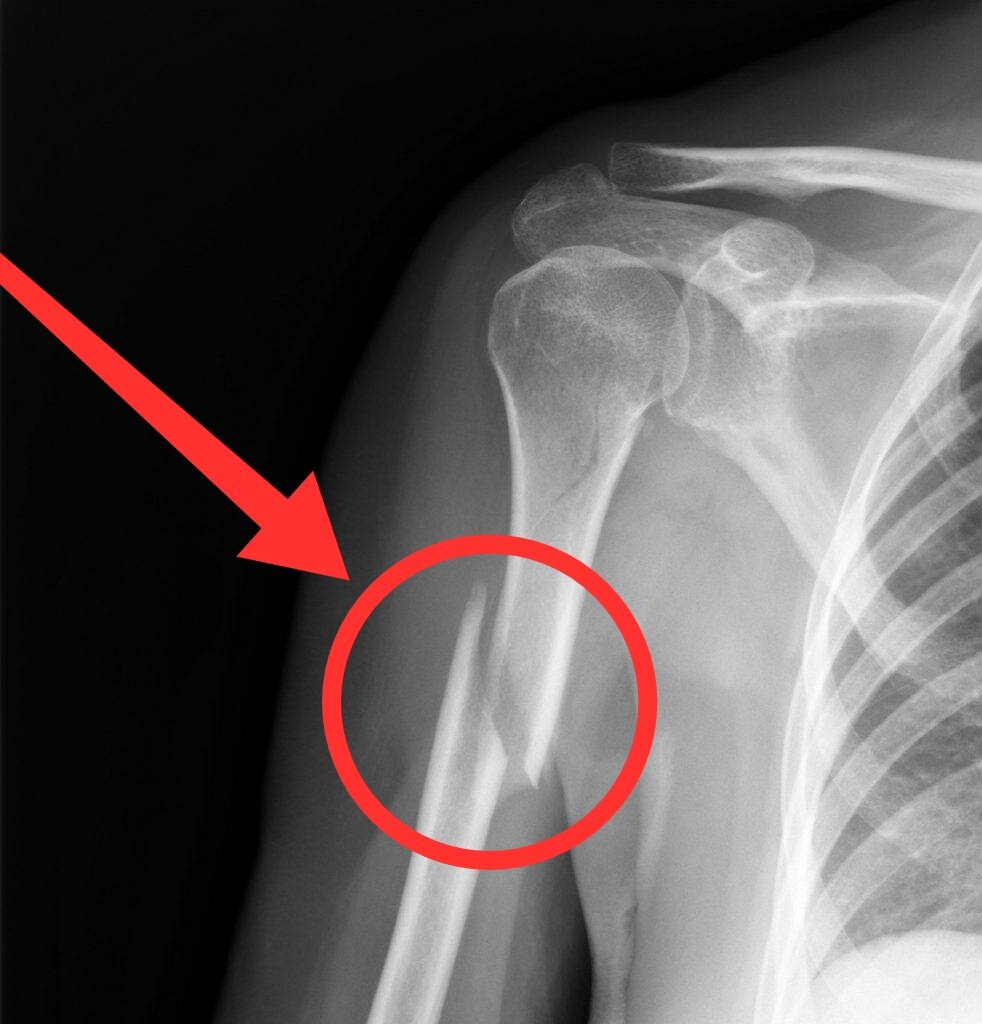

Вообще армрестлинг один из самых безопасных видов спорта, но как не странно случаются переломы. Часто это скрученный перелом плечевой кости со смещением как показано на фото.

При том что это ещё слабо, ведь кость может раздробиться что не даст вам перспективы заниматься этим в будущем.